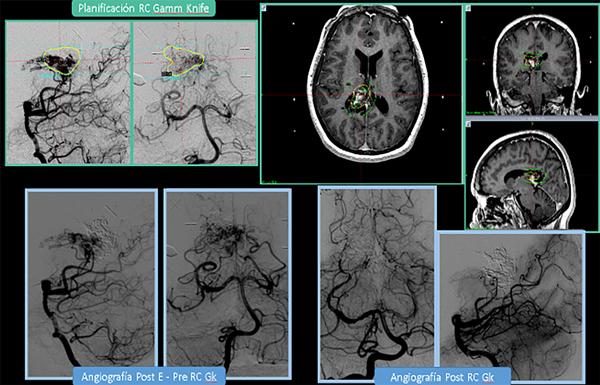

Para las lesiones Grado III “pequeñas” en área elocuente y con drenaje venoso, es decir, las tipo “3–” de Lawton o tipo “B” de Oliveira se indica RC o tratamiento combinado (“E + RC” si el volumen sobrepasa el que es posible tratar de forma segura) (Ver Figura 3). Para las Grado III intermedias incidentales, entre 3 y 6 cm, en área elocuente (o tipo “3 +” de Lawton) se prefiere un manejo conservador; si posee “factor de riesgo angiográfico de ruptura”, un tratamiento multimodal (“E + RC”). En las Grado III intermedias con drenaje venoso profundo (“3”de Lawton) se propone un tratamiento multimodal combinado: “E+ RC”, Vs “E+MC” Vs “RC fraccionada”(Staged o Repeated). En los casos de Grado III únicamente por volumen ( 7 cm, área no elocuente, sin drenaje venoso profundo) sopesar observación vs E+MC según comité de expertos multidisciplinario.

Figura 3: Paciente con MAV SM Grado III: (<3 cm, A. Elocuente + y drenaje venoso profundo +). “3-“ Lawton o “B” Oliveira. A pesar de ser <3cm, el volumen era intermedio. Fue embolizada, y posteriormente tratada con Radiocirugía Gamma Knife (GK). Planificación de GK: A) angiografía estereotáxica. B) RM cerebral del día del tratamiento con GK. Volumen: 4,00 cc. Dosis: 20Gy al 50% de isodosis. Integral D-V: 104,6 m J. C) Angiografías Pre GK. D) Angiografías Post GK (3 años post tratamiento)